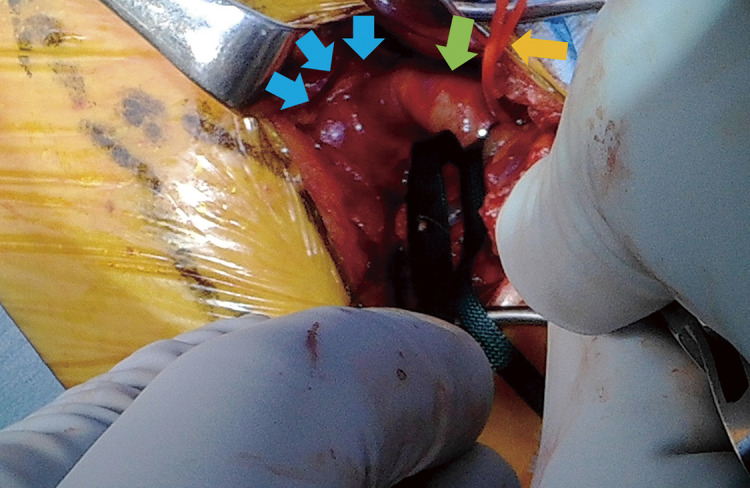

锁骨下动脉瘤是罕见且具有挑战性的治疗,由于其解剖位置和接近关键分支,包括椎动脉。我们报告的情况下,78岁的男子左锁骨下动脉瘤。动脉瘤位于纵隔,直径为31毫米。动脉瘤近端用支架封闭,远端通过锁骨上切口直接结扎。术后影像学证实完全排除。这种混合入路避免了侵入性开放手术,并提供了良好的结果。

Subclavian artery aneurysms are rare and challenging to treat owing to their anatomical location and proximity to critical branches, including the vertebral artery. We report the case of a 78-year-old man with a left subclavian artery aneurysm. The aneurysm was located in the mediastinum and measured 31 mm in diameter. The proximal side of the aneurysm was sealed with a stent graft, while the distal side was accessed through a supraclavicular incision and directly ligated. Postoperative imaging confirmed complete exclusion. This hybrid approach avoided invasive open surgery and provided a favorable outcome.